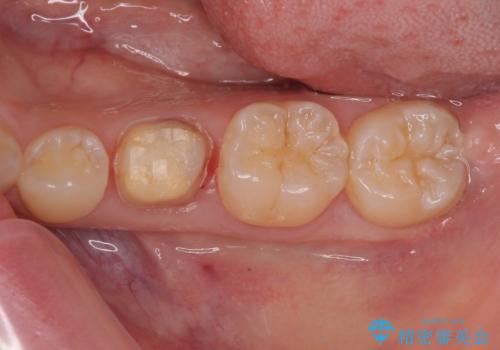

- 左下の乳歯に虫歯ができたので銀歯も外してやり替えたいとのことで来院された患者様です。

レントゲン上で金属の詰め物(メタルインレー)の下に虫歯を認めた為、オールセラミッククラウンでの治療と、乳歯なので予後を考えインプラントによる補綴治療もご提案しましたが、患者様の強い希望によりオールセラミッククラウンでの治療となりました。

拡大鏡視野下で、金属の詰め物(メタルインレー)、虫歯の除去を行い、オールセラミッククラウンに適した形に整えました。